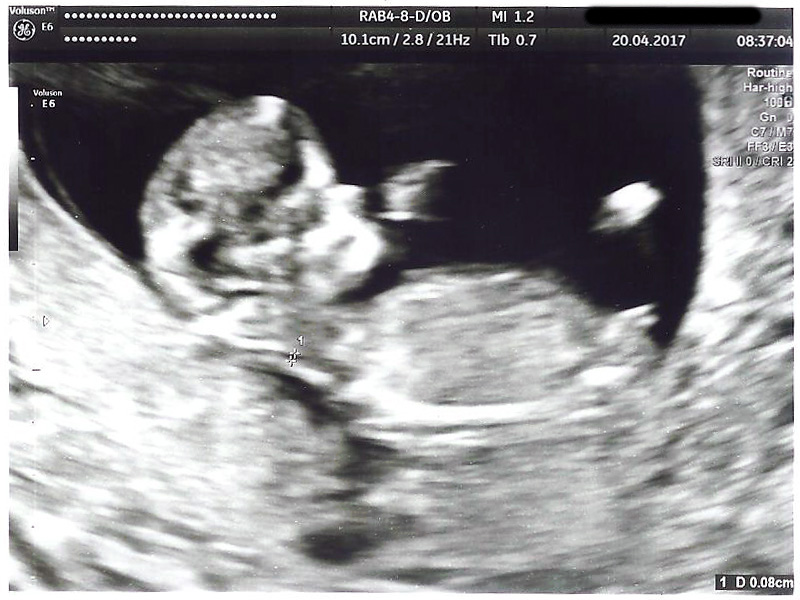

Any predictions based on Ramzi or nub theory? Thanks!

Attachment 35895

Looks like a boy to me :)

Early but boyish [emoji170]